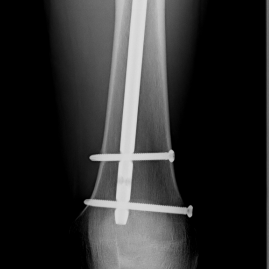

Röntgenbilder

• Knochenbrüche der oberen und unteren Extremitäten